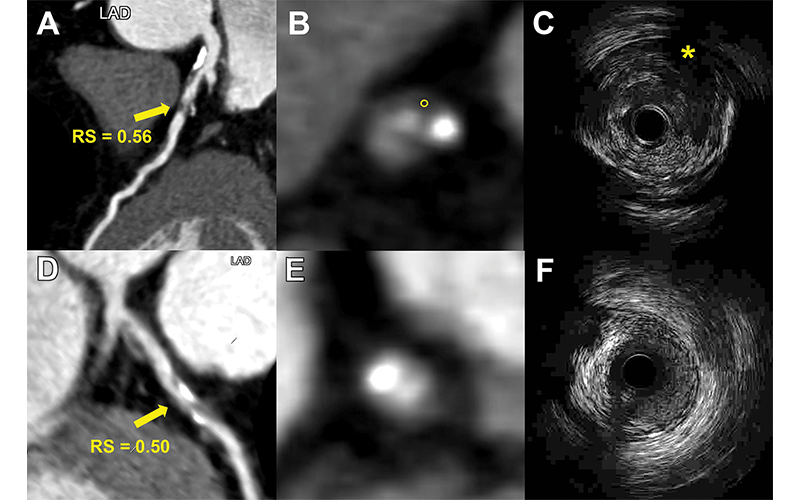

Репрезентативные изображения двух пациентов демонстрируют использование радиомикроскопической сигнатуры (RS) для различения уязвимых бляшек, определяемых с помощью внутрисосудистого УЗИ. (A–C) Изображения изображают уязвимую бляшку с высоким RS. (A) Изображение коронарной КТ-ангиографии (CCTA) показывает частично кальцифицированную бляшку (стрелка) со значением RS 0,56 в проксимальном отделе левой передней нисходящей артерии (LAD). (B) Соответствующее осевое изображение CCTA показывает бляшку с областью низкого затухания (круг, 25 HU). (C) Соответствующее внутрисосудистое УЗИ подтверждает, что бляшка ослаблена (*). (D–F) Изображения показывают неуязвимую бляшку с низким RS. (D, E) Изображения CCTA показывают частично кальцифицированную бляшку (стрелка вГ ) при значении RS 0,50 в проксимальном отделе левой передней нисходящей артерии. (F) Соответствующее внутрисосудистое УЗИ подтверждает наличие бляшки как частично кальцифицированной бляшки без затухания эха и эхопрозрачной зоны. Высокое или низкое поражение RS определяли с использованием оптимального порогового значения 0,53 (диапазон 0,46–0,58).